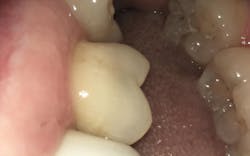

Case D: Desensitizing

The patient stated she felt cold sensitivity occurring on the upper left between nos. 14 and 15. Slight gum recession was noted on the buccal surface of no. 15 (figure 3). After a prophy was completed, the tooth was isolated with a cotton roll and tufted floss was placed interproximally on 14/15. SDF was brushed on the tooth for one minute along the buccal gumline of no. 15 and interproximally. No staining occurred. The patient stated she felt instant relief while drinking cold water. The code for tooth sensitivity is D9910: Application of desensitizing medicament per visit.